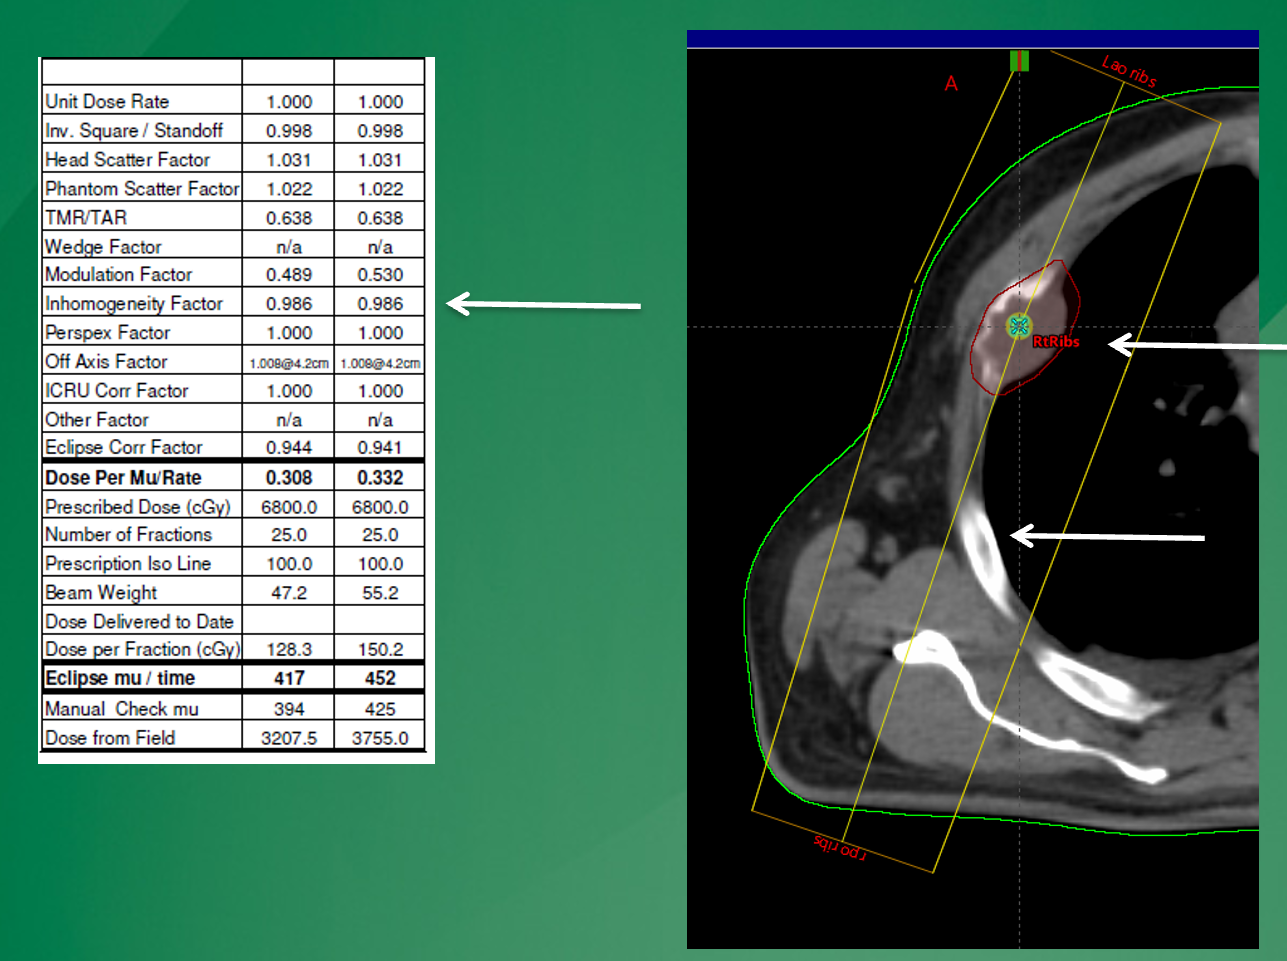

How does spreadsheet (1D) calculation compare to TPS 3D calculation (e.g., Eclipse Treatment Planning System)?

Spreadsheet calculations are simplified, while TPS uses more sophisticated 3D algorithms

why may the 1D calculation (left) show a different MU value than the Eclipse calculation on the right?

simple 1D calculations will only account for heterogeneities lying along the central axis. in this case, the centra axis does not go through rib and through lung so there is not as significicant of a homogeneity calc than that seen in eclipse, that will account for the entire beam